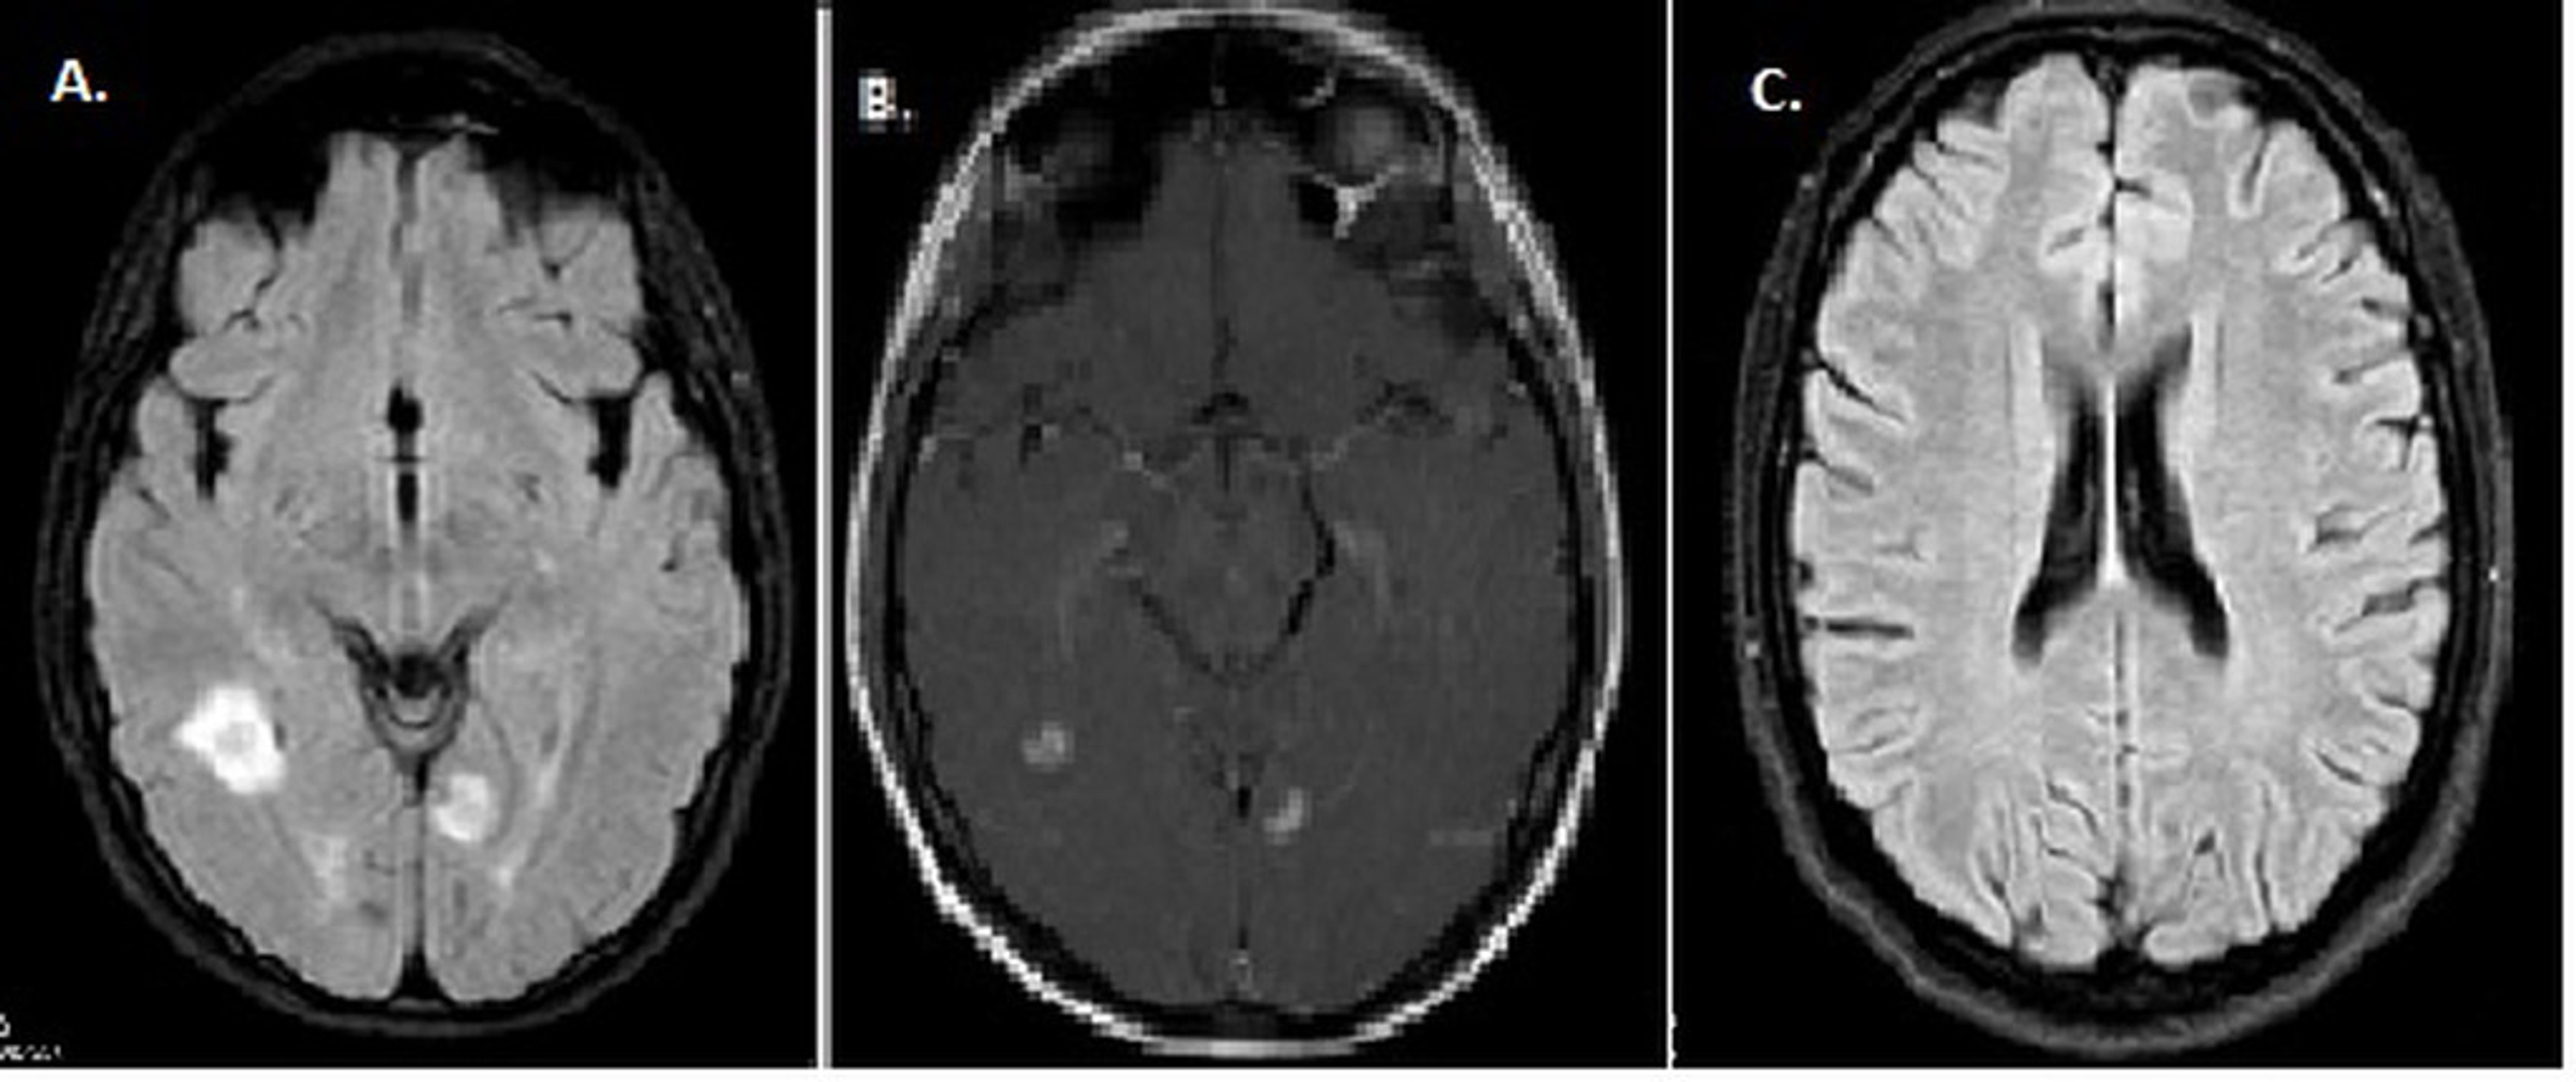

MRI of the brain showing demyelinating plaques in the medulla oblongata

a, b, c. MRI revealed demyelinating plaques in the pons, and temporal Demyelinating Plaques Brain Your healthcare provider may be able to locate plaques or lesions affecting. The pathologic hallmark of multiple sclerosis (ms) is the presence of focal demyelinated lesions with partial axonal. Brain signals can’t move across scar tissue as quickly, so your nerves don’t work as well as they should. Mri is the imaging modality of choice to assess demyelinating disorders of. Demyelinating Plaques Brain.